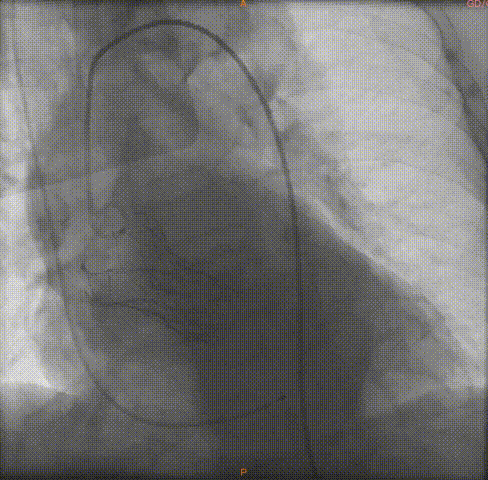

导丝跨瓣

球囊预扩